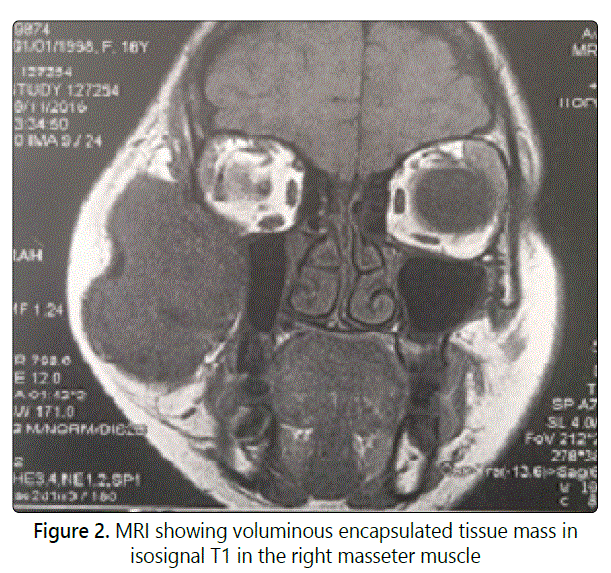

Case report: We report in this article a case of an Haemangioma involving masseter muscle in a 16-year-old girl referred for progressive and unsightly swelling of the right cheek present since 2-years. Clinical examination showed a painless, well circumscribed, and firm swelling in the right cheek. Facial CT Scan with contrast injection revealed a highdensity region in the right masseteric muscle without bone lysis. MRI showed voluminous encapsulated tissue mass in isosignal T1 and T2 in the right masseter muscle. The patient was operated externally by performing an exo-facial parotidectomy with tumorectomy. Discussion: The masseter muscle localization of intramuscular hemangioma represents the most common site (36%), followed by trapezius. Excessive muscle contractions and trauma seem to be important factors in the development of this type of malformation. It is a mass of variable size, unique, mobile and firm. CT and MRI have significantly increased the accuracy of preoperative diagnosis for this lesion. They allow to define precisely its limits and its relations with the neighboring tissues. The treatment of choice is surgical excision of whole lesion with adjacent muscle.

A healthy 16-year-old girl was referred for evaluation and management of progressive, unsightly swelling of the right cheek. The swelling had been present since 2-years and had gradually increased in size. No prior history of trauma, dental problems, trismus or other medical problems was noted. Clinical examination showed a big swelling in the right cheek, measuring 9 cm x 4 cm, painless, well circumscribed, and firm (Fig 1). The overlying skin was freely moveable and not discolored. No pulsation or collateral venous circulations were noted. There was no lymphadenopathy. The patient was otherwise asymptomatic. Facial CT Scan with contrast injection revealed a high-density region in the right masseteric muscle measuring 31 x 47 x 83 mm without bonelysis. MRI showed voluminous encapsulated tissue mass in isosignal T1 and T2 in the right masseter muscle (Fig 2). The arteriography showed a vascularised mass by a branch of the maxillary artery. Preoperative diagnosis was hemangioma of the masseter muscle and surgery was scheduled after arterialembolization. The patient was operated externally by performing an exo-facial parotidectomy with tumorectomy by taking a little part of the masseter muscle (Fig 3). The operative sequences were simple, with facial paresis.